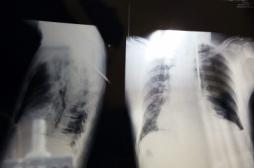

LES MALADIES

SYMPTÔMES